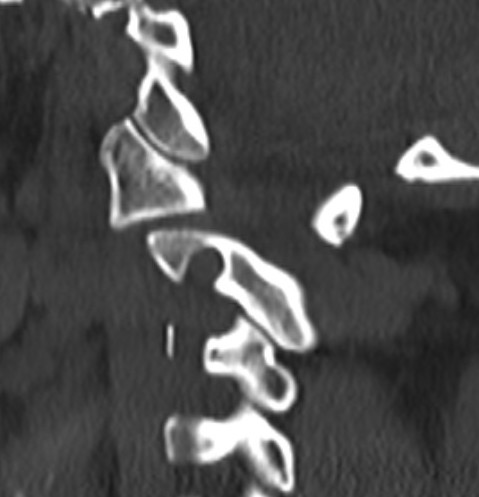

CT Scan

Atlanto-axial rotatory instability

Classification Fielding & Hawkins

| Type I |

Unilateral facet subluxation / dislocation ADI < 3 mm |

Transverse ligament intact | Most common |

| Type II |

Unilateral facet subluxation / dislocation Anterior displacement of the atlas by 3–5 mm ADI 3 - 5 mm |

Transverse ligament injury | |

| Type III |

Bilateral facet subluxation / dislocation Anterior displacement of atlas by more than 5 mm ADI > 5 mm |

Alar and tranverse ligament deficient Both lateral masses displaced anteriorly |

|

| Type IV | Posterior displacement of atlas | Ondontoid process deficient or fractured |

Rare Highest risk of neurological injury |